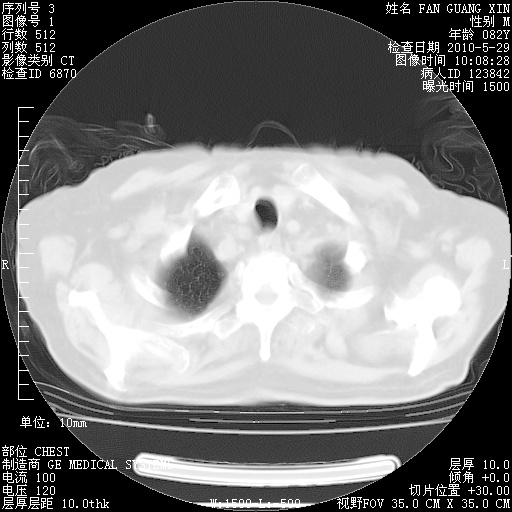

发表于 2010-5-19 19:23

还需要哪些辅助检查?我们医院排除真菌感染没有任何检验方法,胸片好像能够排除肺部真菌感染。

补充:ENA化验全部阴性。免疫五项(IgG、IgA、IgM、C3、C4)只有C4略高。